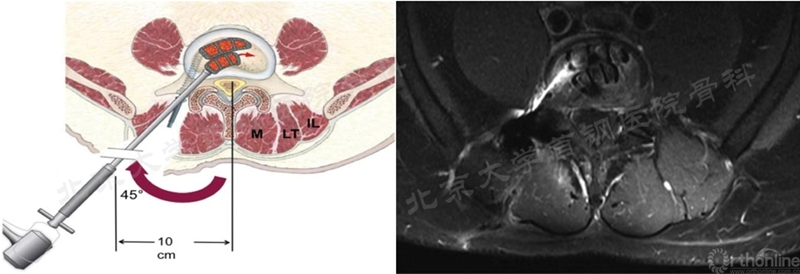

在双通道融合技术不断发展下,2020年8月韩国Min Seok Kang教授第一次报道了双通道下的ELIF并将其命名为BE-EFLIF。作者应用椎旁入路的方式,切口在椎弓根外缘2cm处。经过Kambin三角进行椎间隙处理和Cage斜插入,再经quarterback切口将cage横置(如图16),取得了十分满意的效果。这篇论文影响重大,开创了双通道下进行椎间融合新的手术模式。

图16 BE-ELIF手术入路及术中镜下视野、Cage横置过程(图片来源于文献)